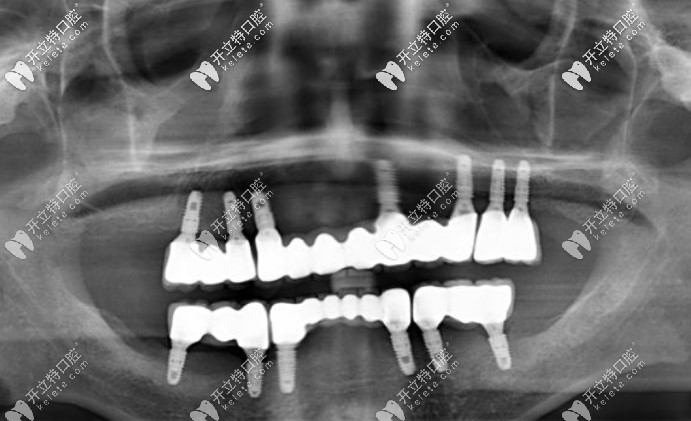

全口種植后拍的片子▼

在美奧口腔做全口種植牙效果圖